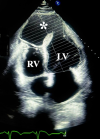

Therapeutic interventions: on December 23, 2024, the patient underwent open-heart surgery. A large LV apical pseudoaneurysm and a post-infarction VSD were identified (Figure 3). The septal defect was closed with pledgeted sutures, followed by left ventricular remodeling (Dor procedure) and LIMA-to-LAD bypass grafting. Postoperative echocardiography confirmed successful shunt closure and graft patency.

Figure 3: intraoperative photograph demonstrating the performed thoracotomy; pseudoaneurysm measuring 7.0 x 5.5 cm is visible in the antero-apical region of the left ventricle